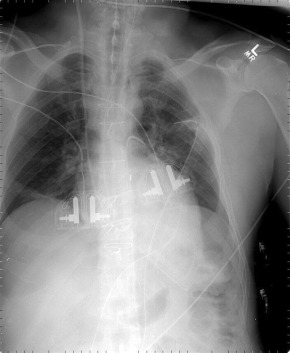

The Impella 2.5 (2.5 L/minute support), a continuous flow ventricular assist device, provides continuous flow assist comparable to that of intra-aortic balloon pump. It is percutaneously inserted from the groin. Radiographically and fluoroscopically, the pigtail tips are apparent, the mechanical intake device and the mechanical output device are obvious and the conduit between the two is fairly obvious, and the more proximal catheter is marked by a faint radiopaque stripe. The pigtail tip holds the intake back from the apical wall; the intake housing draws ventricular cavity blood into it, and the output housing with the impeller pump draws blood through the intake housing and ejects it into the aortic root on the far side of the aortic valve, offloading and resting the left ventricle. On a frontal radiograph, the pigtail is directly left inferiorly and the conduit initially follows the same line before it angulates vertically or vertically/leftward up the aortic root.